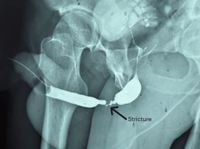

°í¾Ð ÄÉÀÌºí¿¡ °¨ÀüµÇ´Â »ç°í¸¦ ´çÇÑ ÈÄ, ¼ö³âÀÌ Áö³ª ¼Òº¯ ±æÀÌ ¸·Çô¹ö¸° 30´ë ³²¼ºÀÇ »ç·Ê°¡ º¸°íµÆ´Ù.¸ð·ÎÄÚ ¹°·¹ÀÌÀ̽º¸¶ÀÏ ±ºº´¿ø ºñ´¢±â°ú ÀÇ·áÁø¿¡ µû¸£¸é 33¼¼ ³²¼ºÀº ÀÛ¾÷ Áß ±Ý¼Ó ¹°Ã¼°¡ Àü¼±°ú Á¢ÃËÇϸé¼..